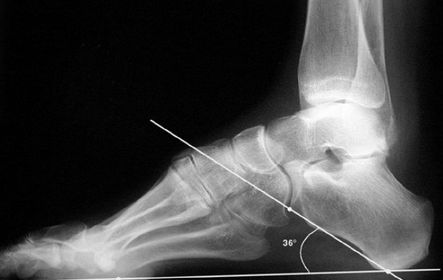

What foot type does this calcaneal inclination angle indicate? | Pes cavo-varus |

What is this angle called? What foot type does it indicate | Talar - 1st MT or Meary's Angle Pes cavo-varus |